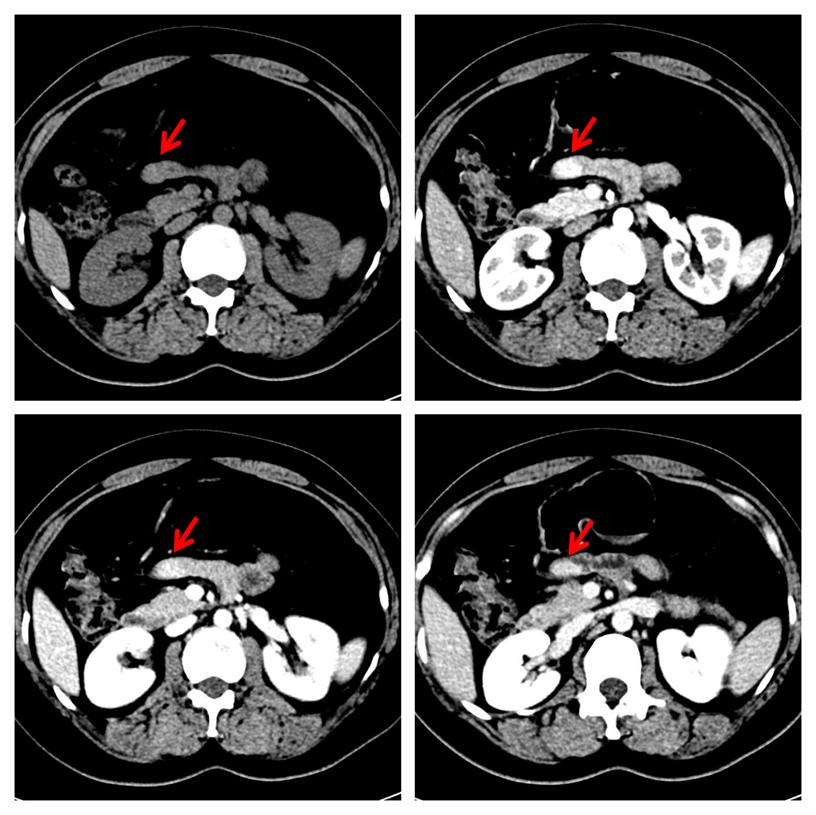

中年女性,2年前因"右胸壁惡性黑色素瘤"行手術治療,平素無腹脹、腹痛、惡心、嘔吐等不適癥狀。本次常規復查,行增強CT檢查發現小腸結節,考慮神經內分泌腫瘤可能大(圖1)。本次發病以來,精神、飲食、睡眠差,近2 日有少量便血,小便無異常。體格檢查:腹部平坦,未見腸型及蠕動波,腹肌軟,無壓痛及反跳痛,腸鳴音弱。實驗室檢查:消化道腫瘤標志物(甲胎蛋白、癌胚抗原、糖類抗原19-9、糖類抗原72-4)、血常規、肝腎功能均在正常范圍內。

圖1,增強CT檢查示小腸結節(紅箭),明顯強化